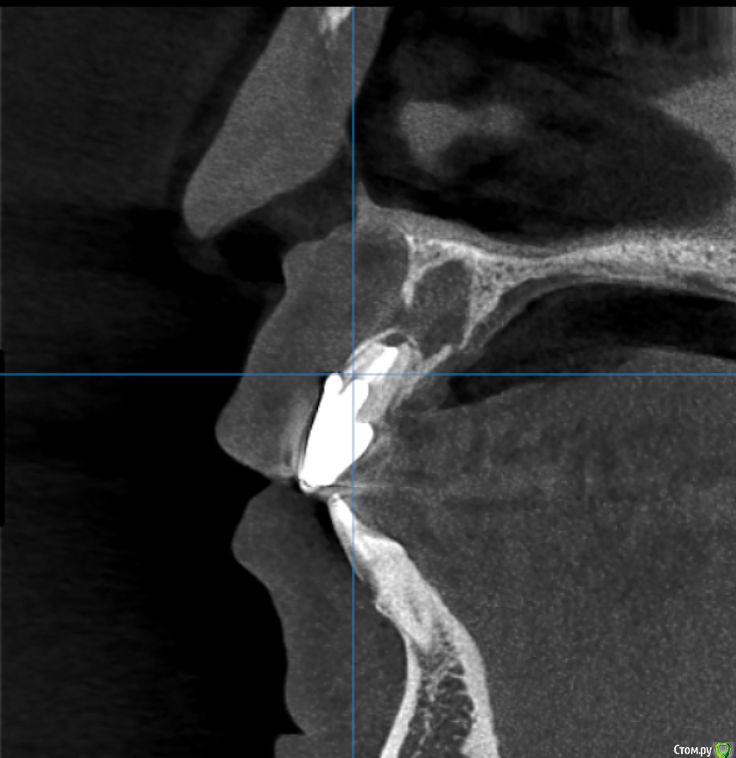

Kazankov.Egor Опубликовано 6 июля, 2018 Поделиться Опубликовано 6 июля, 2018 (изменено) Жалобы на неприятный запах изо рта, предположительно от 11 зуба. В анамнезе РВК 11 зуба.Скрины кт прилагаю. Пациент девушка, естественно, главный вопрос -эстетика. Нужна помощь по тактике. Изменено 6 июля, 2018 пользователем Kazankov.Egor Ссылка на комментарий

Kazankov.Egor Опубликовано 7 июля, 2018 Автор Поделиться Опубликовано 7 июля, 2018 Визуально, небольшая рецессия десны, кариес цемента. Ссылка на комментарий

Kazankov.Egor Опубликовано 7 июля, 2018 Автор Поделиться Опубликовано 7 июля, 2018 Если зуб под коронкой не сгнил, то ревизия периапикальных тканей и ретроградная пломбировка канала.А с кистой несонобного канала как поступить? Ссылка на комментарий